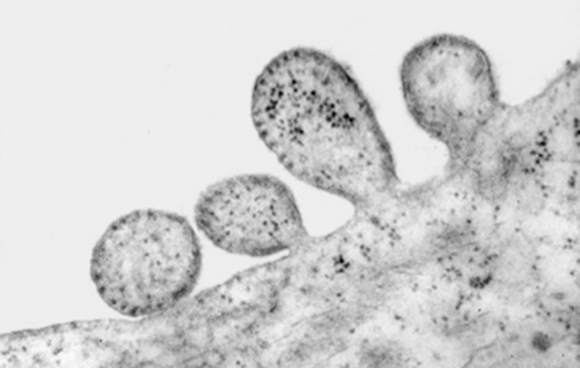

נגיף החצבת בתהליך הנצה מתא חולה| צילום במיקרוסקופ אלקטרונים: פרופ' שמואל רוזנבלט, אונ' ת"א